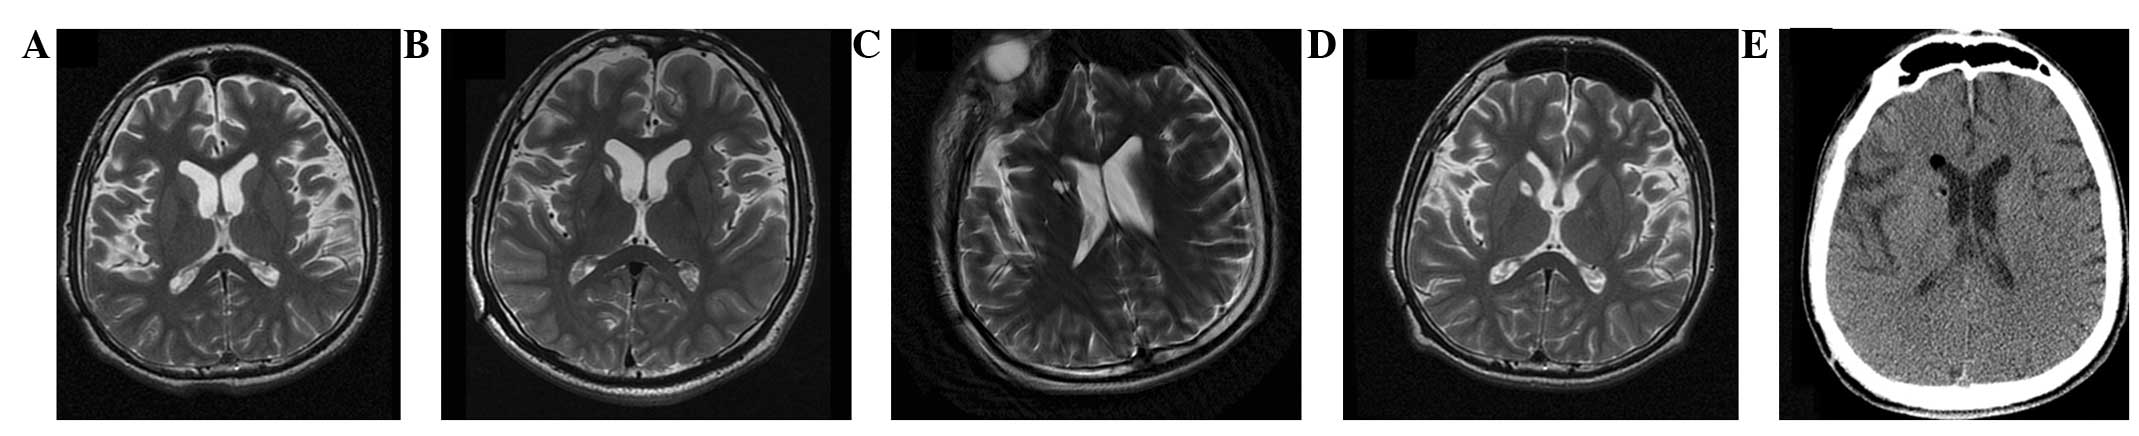

圖2:-T2加權磁共振成像 (MRI)

(A) 術(shù)前 MRI 顯示腦萎縮。 (BD)術(shù)后1年、3年、4年MRI與術(shù)前MRI相比無(wú)明顯變化。 (E) 術(shù)后3天,計算機斷層掃描顯示沒(méi)有出血或水腫。

遺傳分析發(fā)現患者DYT1 ( TOR1A )第五外顯子存在突變 (907-909 delGAG) 。他對神經(jīng)外科手術(shù)表現出良好的耐受性,并于4點(diǎn)出院。沒(méi)有與細胞植入或外科手術(shù)相關(guān)的嚴重不良事件。POD時(shí)的CT掃描顯示沒(méi)有出血或水腫(圖2e)。術(shù)后1個(gè)月,患者的PTD癥狀開(kāi)始改善。BFMDMS逐漸增加,從術(shù)前的21分別增加到術(shù)后1、2、3和4年的18、17、15和13,術(shù)后4年改善38.1%(表1)。

CT(圖1b-e)和MRI(圖2b-d)掃描顯示4年隨訪(fǎng)期間沒(méi)有顯著(zhù)變化。 手術(shù)前1天(圖1f)和手術(shù)后1、2、3和4年(圖1g-j) 獲得18F-FDGPET掃描。術(shù)后雙側植入部位豆狀核和丘腦18F-FDG攝取值較術(shù)前增加。這一結果表明,自移植以來(lái),葡萄糖代謝逐年略有增加。